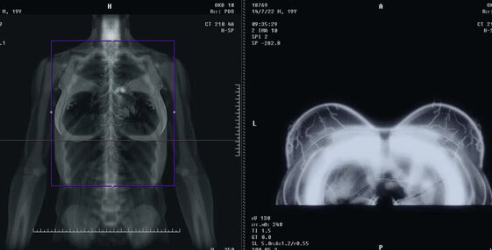

유방암은 조기 발견이 중요하기 때문에 정기적인 검진이 필요해요. 검진 방법에는 유방 촬영술, 초음파 검사, MRI 등이 있어요.

- 초음파 검사: 유방 조직이 치밀해 촬영술로 구분이 어려울 때 초음파 검사가 도움이 돼요. 30대 이상의 여성도 추천됩니다.

- MRI: 유방암 가족력이 있거나 고위험군에 해당하는 여성에게는 MRI 검사가 유용해요. 더 정밀하게 종양의 위치와 크기를 확인할 수 있어요.